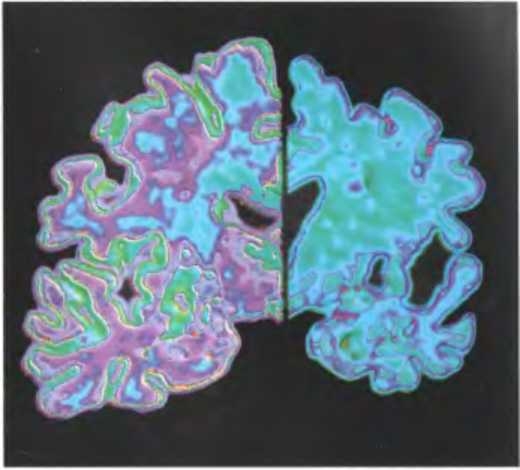

На приведенных здесь иллюстрациях (если верить создателям программы, с помощью которой они обработаны) видна разница между мозгом человека, говорящего правду (слева), и человека, который лжет (справа). Полагают, что дополнительная активность, наблюдаемая во втором случае, связана с дополнительными когнитивными усилиями, которые требуются для подавления естественного стремления рассказывать все как есть и для измышления правдоподобной лжи. Такие результаты позволяют предположить, что по умолчанию наш мозг настроен на то, чтобы говорить правду, а ложь представляет собой сложное усовершенствование, требующее постоянной доработки.

По мере развития болезни Альцгеймера мозг сморщивается и уменьшается в размерах. Здоровый мозг [слева) и мозг человека с ярко выраженными симптомами болезни Альцгеймера (справа).